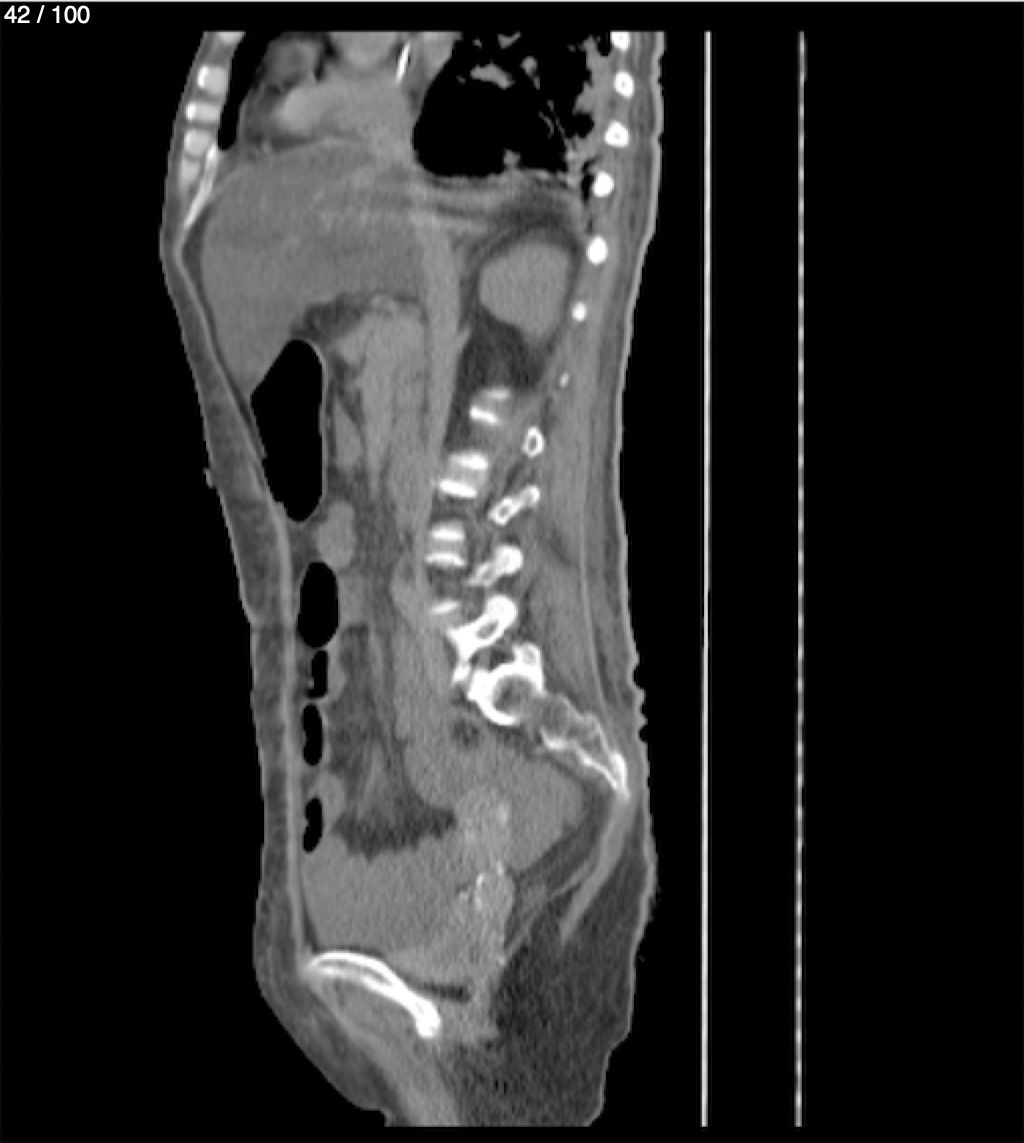

Hilda Geronimo Mendez 60A - T.C Abdomen Simple